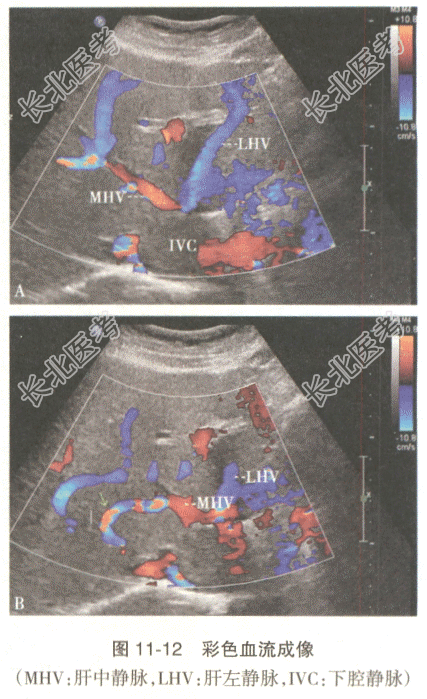

- 多项选择题2.[提示]进一步超声检查显示双肾静脉、双下肢静脉未见明显异常(图11-12A)。下腔静脉内病变与心脏占位相延续,并累及双侧髂总、髂内静脉、子宫静脉、子宫肌壁间静脉。病变内部可见多处纤细纵行短条状静脉血流。肝静脉的声像图表现如图11-12B。考虑本病是

A、布加综合征

B、静脉内平滑肌瘤病

C、下腔静脉血栓形成

D、下腔静脉癌栓

E、下腔静脉血管内皮瘤

F、系统性血管炎